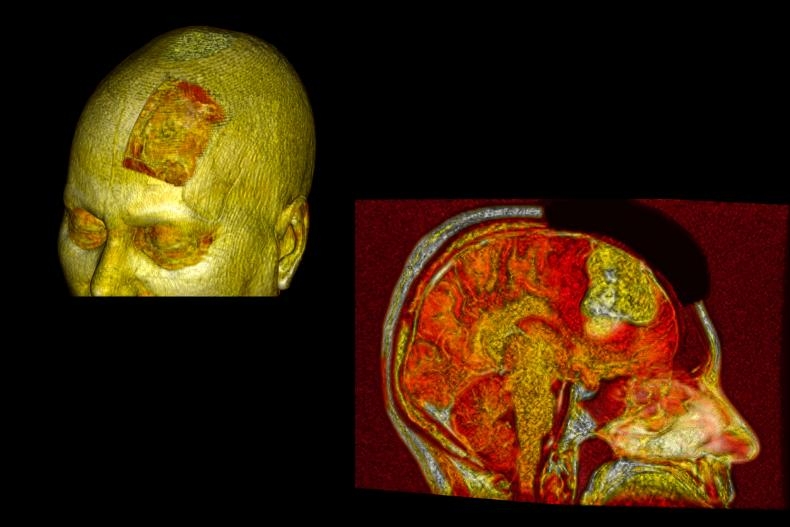

Brain Tumor Surgery: Maximal Safe Resection, Not Maximal Resection

Brain tumor surgery requires a delicate balance between oncological goals and preservation of neurological function. Although traditional approaches emphasized the extent of resection, contemporary literature highlights that functional preservation is at least as important as survival.

According to the Less Is One principle:

- The surgical objective is maximal safe resection, not maximal resection.

- Surgical planning prioritizes preservation of eloquent cortex, deep nuclei, and white matter tracts.

- In cases with a high risk of neurological deficit, subtotal resection combined with adjuvant therapies may represent a deliberate and appropriate choice.

- The use of neuronavigation and intraoperative neuromonitoring now enables maximal tumor removal with minimal damage.

This approach aims to preserve postoperative neurological function and improve patients’ quality of life.

Beyond neurological and oncological outcomes, this precision-oriented surgical strategy also yields substantial functional and economic benefits. By minimizing unnecessary tissue damage and avoiding overly aggressive resections, patients experience less postoperative functional impairment, shorter hospital stays, and reduced need for prolonged rehabilitation. Preservation of neurological function facilitates an earlier return to daily activities and professional life, thereby limiting workforce loss and productivity decline. From a healthcare system and insurance perspective, reduced hospitalization duration and lower long-term disability rates translate into significant cost savings and improved resource efficiency. Consequently, maximal safe resection not only optimizes clinical outcomes but also represents a sustainable and economically responsible model in modern brain tumor surgery.